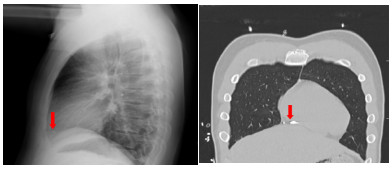

1 资料与方法患者男性,17岁,因“左前臂异物8 h”于2022-05-23 21:25收住急诊抢救室。患者8 h前修车时敲打金属物品,小片金属飞溅至左前臂,伴少量出血,无麻木等不适主诉。后立即于当地医院就诊,X线示异物位置如图 1,当地医院建议转上级医院。上级医院再次行X线检查(图 2),后予以臂丛麻醉下行“左上肢清创+异物取出术”术中未见异物,术后复查X线,左上肢,左肩部以及左侧胸部未见异物,嘱立即转至本院。

| 图 2 外伤后第二次评估异物位置X光检查图像 |

患者入院后无胸闷气促等不适主诉。入科查体:体温36.5 ℃,脉搏86次/min,呼吸频率16次/min,血压106/54 mmHg(1 mmHg=0.133 kPa),指尖氧饱和度99%~100%(未吸氧情况下),神清,瞳孔等大等圆,对光反射可,双肺呼吸音清,无明显干湿啰音,听诊心脏,律齐,无病理性杂音,左侧前臂近端及远端各一创面包扎,敷料干燥,未见明显渗出,左上肢肌力无法配合(考虑臂丛阻滞麻醉未完全恢复),余四肢肌力肌张力感觉无明显异常。立即完善相关检查(图 3、4),通过X线以及CT定位异物,超声评估异物在心脏中的活动情况及与心脏搏动时与瓣膜以及周围组织结构关系,可见异物在心脏内较固定,未影响瓣膜运动。同时血化验(动脉血气、感染指标、心肌酶谱、肌钙蛋白、D二聚体等)及心电图未见明显异常,请心胸外科会诊后建议暂予以抗炎保守对症处理。